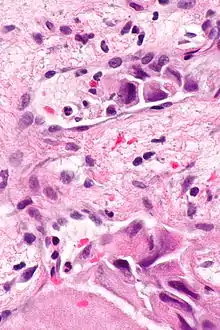

Lymphovascular invasion (LVI or lymphovascular space invasion) is the invasion of a cancer to the blood vessels and/or lymphatics.

Lymphovascular invasion, especially in carcinomas, usually precedes spread to the lymph nodes that drain the tissue in which the tumour arose. Conversely, cancers with lymph node spread (known as a lymph node metastases), usually have lymphovascular invasion. Lymph node metastases usually precede secondary tumours, i.e. distant metastases.